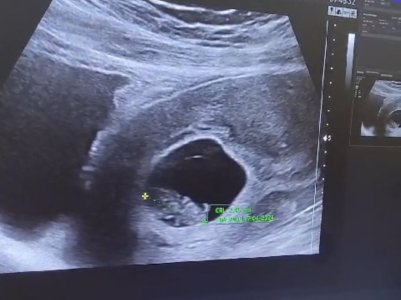

Kızlar herkese selam ! 8 haftalık gebeyim ve hemen hemen her anne adayı gibi cinsiyetini aşırı merak ediyorum. Tabikide önceliğim sağlıklı olması bunu söylemeye bile gerek yok, bizimki biraz olayım heyecanı :) Ramzi teorisi diye bir şey gördüm konudan anlayan ekteki ultrasonda fotoğrafıma göre cinsiyetiyle ilgili tahminde bulunabilir mi acaba?

RAMZİ TEORİSİ VE CİNSİYET TAHMİNİ

Kimler kimler yazdı?Kızlar herkese selam ! 8 haftalık gebeyim ve hemen hemen her anne adayı gibi cinsiyetini aşırı merak ediyorum. Tabikide önceliğim sağlıklı olması bunu söylemeye bile gerek yok, bizimki biraz olayım heyecanı :) Ramzi teorisi diye bir şey gördüm konudan anlayan ekteki ultrasonda fotoğrafıma göre cinsiyetiyle ilgili tahminde bulunabilir mi

Kız bebek duruyor karından mı bakılmıştı belli olmuştur büyük ihtimal cinsiyetiKızlar herkese selam ! 8 haftalık gebeyim ve hemen hemen her anne adayı gibi cinsiyetini aşırı merak ediyorum. Tabikide önceliğim sağlıklı olması bunu söylemeye bile gerek yok, bizimki biraz olayım heyecanı :) Ramzi teorisi diye bir şey gördüm konudan anlayan ekteki ultrasonda fotoğrafıma göre cinsiyetiyle ilgili tahminde bulunabilir mi acaba?

Kız gibi duruyor ne acabaaKızlar herkese selam ! 8 haftalık gebeyim ve hemen hemen her anne adayı gibi cinsiyetini aşırı merak ediyorum. Tabikide önceliğim sağlıklı olması bunu söylemeye bile gerek yok, bizimki biraz olayım heyecanı :) Ramzi teorisi diye bir şey gördüm konudan anlayan ekteki ultrasonda fotoğrafıma göre cinsiyetiyle ilgili tahminde bulunabilir mi acaba?

Canım göbekten bakildiysa erkekKızlar herkese selam ! 8 haftalık gebeyim ve hemen hemen her anne adayı gibi cinsiyetini aşırı merak ediyorum. Tabikide önceliğim sağlıklı olması bunu söylemeye bile gerek yok, bizimki biraz olayım heyecanı :) Ramzi teorisi diye bir şey gördüm konudan anlayan ekteki ultrasonda fotoğrafıma göre cinsiyetiyle ilgili tahminde bulunabilir mi acaba?

Bana da yorum lütfen karından 10 haftaCanım göbekten bakildiysa erkek

Merhaba sizce nedirRamzi teorisine göre kız gibi duruyor. cinsiyetiniz belli oldu mu acaba ?